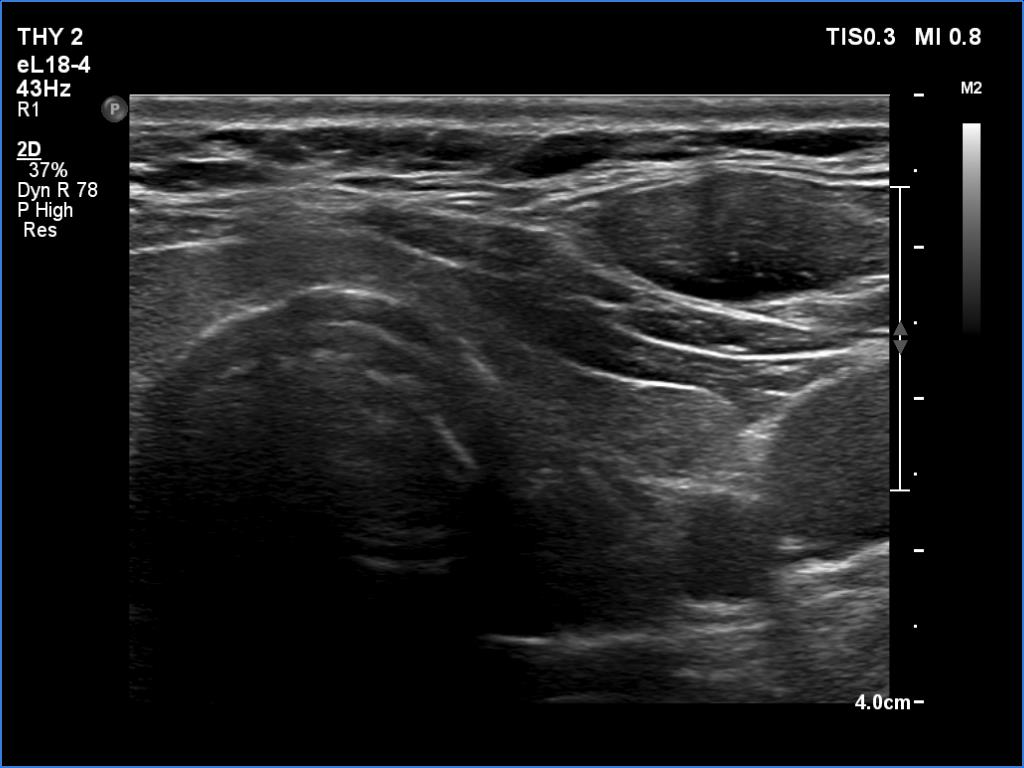

Ultrasonography. The thyroid was echonormal and had several small cystic lesions without any clinical or oncological importance. According to the palpable mass, a moderately hypoechoic lesion was detected several centimeters under the thyroid in the middle of the neck. The lesion was within the muscle tissue. It was homogeneous and presented no vascularity.